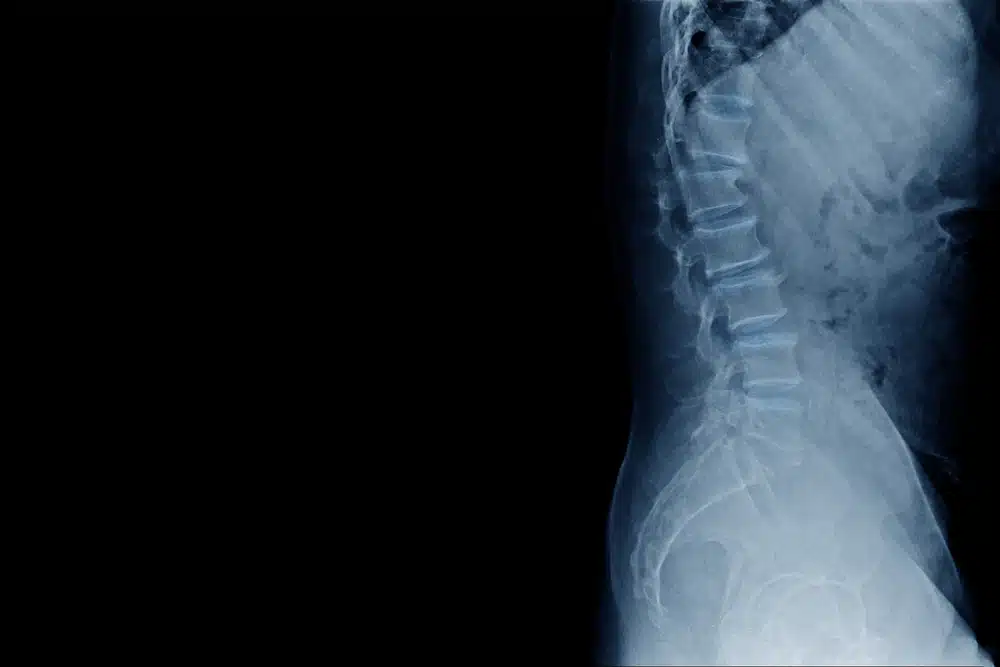

Spinal cord stimulators are implantable medical devices that deliver electrical pulses to the spinal cord to manage chronic pain. They were marketed as a long-term solution for patients whose pain can not be controlled with traditional medications or surgery.

However, instead of offering relief, many patients began experiencing serious complications. Reports surfaced of devices malfunctioning, wires migrating inside the body, and electrical currents causing further nerve damage rather than easing pain. Sometimes, patients require emergency medical care or multiple revision surgeries to remove or replace the defective device.